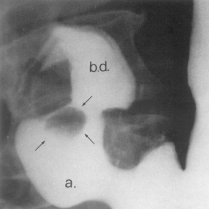

Semnele directe Nisa - imagine de plus de substanta de contrast, corespunzatoare escavatiei peretelui gastric. Din profil imaginea iese din conturul ipotetic al stomacului

Are o forma rotund - ovalara si este dispusa, de obicei, perpendicular.Marimea nisei este variabila, De cele mai multe ori, nisa se localizeaza la nivelul micii curburi în vecinatatea unghiului gastric, dar o putem întâlni si la nivelul micii curburi orizontale, a marii curburi, precum si la nivelul fetelor.

În jurul nisei, exista o reactie inflamatorie edematoasa care se vizualizeaza ca o linie lacunara - linia Hampton bine delimitata, având o grosime uniforma (gulerul ulcerului).